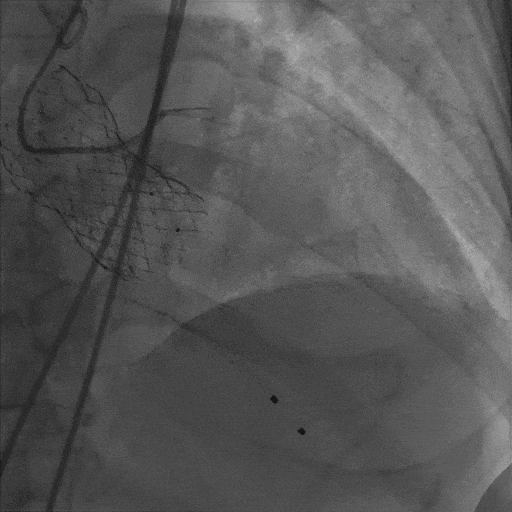

最终造影

入路检查

LVEF:57%,LVEDD:62mm,LVESD:43mm,主动脉瓣功能正常,瓣周漏(少量),二尖瓣中度反流,三尖瓣中度反流。